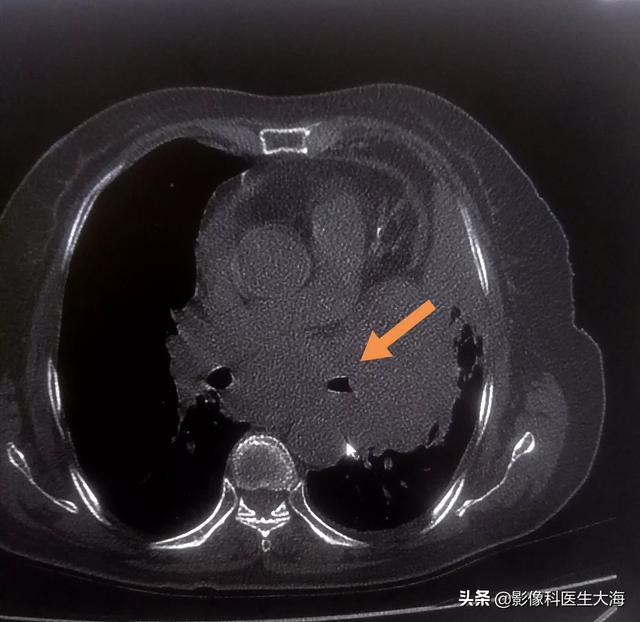

Certains patients atteints d'un cancer du poumon présentent soudainement un enrouement et des difficultés de prononciation. De nombreuses personnes pensent qu'il s'agit d'un refroidissement et d'une gorge muette, ou que les cordes vocales ne sont pas en cause, puis se rendent dans un service d'ORL pour effectuer une laryngoscopie. En fait, l'enrouement des patients atteints de cancer du poumon est dû à la compression du nerf laryngé récurrent par la tumeur.

Le cancer central du poumon a une probabilité plus élevée de provoquer un enrouement du larynx, avec un taux d'occurrence de plus de 40 %. Il peut s'agir d'une invasion directe du nerf laryngé récurrent par la tumeur pulmonaire ou d'une compression du nerf laryngé récurrent par les ganglions lymphatiques médiastinaux hypertrophiés et métastatiques. Pourquoi la compression du nerf laryngé provoque-t-elle un enrouement ?

Le nerf laryngé récurrent est divisé en branches antérieure et postérieure des deux côtés du corps humain, la branche antérieure innervant les muscles internes des cordes vocales et la branche postérieure les muscles adducteurs des cordes vocales. Le nerf laryngé récurrent est divisé par le nerf vague et passe dans le sillon trachéo-œsophagien à gauche et à droite, qui peut être paralysé par une légère traction ou un contact direct. Le nerf laryngé récurrent gauche est plus long et plus profond que le droit, il est donc plus susceptible d'être touché. Une lésion unilatérale de la branche entière ou de la branche antérieure du nerf laryngé récurrent provoque un enrouement, qui peut sérieusement affecter le travail et la vie du patient, mais n'affecte pas la respiration et la déglutition. Une lésion des deux côtés du nerf laryngé récurrent se manifeste par une perte de la voix, une dyspnée et, dans les cas les plus graves, une asphyxie.

Si l'enrouement d'un patient atteint d'un cancer du poumon s'aggrave progressivement sans aucun signe d'amélioration, il est pratiquement certain qu'il est causé par la tumeur qui comprime ou empiète sur le nerf laryngé récurrent ; un scanner du thorax et une laryngoscopie peuvent alors être effectués pour clarifier l'état de la maladie. Si la laryngoscopie révèle une paralysie des cordes vocales, il est certain que le nerf laryngé récurrent est endommagé. Si le nerf laryngé récurrent est seulement comprimé, il peut être détaché chirurgicalement, mais il n'y a pratiquement aucune chance d'intervention chirurgicale en cas d'invasion du nerf laryngé récurrent causée par une tumeur maligne. L'invasion du nerf laryngé récurrent par un cancer central du poumon ou la compression du nerf laryngé récurrent par des ganglions lymphatiques médiastinaux signifie que la tumeur est avancée.